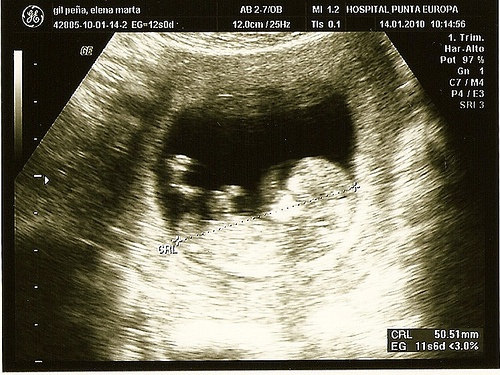

Ecografia o ultrasuoni

Serve sia per individuare dei problemi, sia per ottenere le prime immagini del vostro bambino. Questa tecnica aiuta a scoprire il sesso del bambino, ma anche a identificare le prime anomalie visibili, come difetti del cuore o alterazioni dei cromosomi.

Le ecografie di secondo livello, invece, sono un esame consigliato per osservare da vicino possibili difetti del feto. Si consigliano quando, negli esami di routine, è stata identificata un’anomalia. La tecnica non è invasiva: un apparecchio produce un’immagine grazie a ultrasuoni che, senza nuocere al bambino, permette di osservare l’ambiente interno dell’utero.